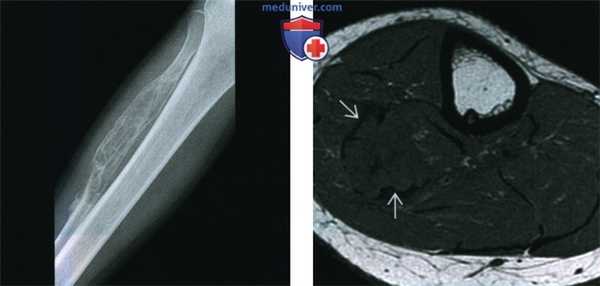

(Слева) МРТ, аксиальная проекция, режим Т2, с подавлением сигнала от жира: у этого же пациента определяется область преимущественно низкоинтенсивного сигнала, окруженная зоной умеренно выраженного отека. Низкоинтенсивный сигнал занимает большую часть патологического очага. Десмопластическая фиброма является внутрикостной формой фиброматоза или мягкотканного десмоида. Такое новообразование встречается редко, его наличие можно предполагать при умеренно агрессивном костном очаге, большая часть которого имеет сигнал низкой интенсивности в режиме Т2.

(Справа) МРТ, сагиттальная проекция, режим Т1, с подавлением сигнала от жира и контрастированием, этот же пациент: очаге контрастным усилением.